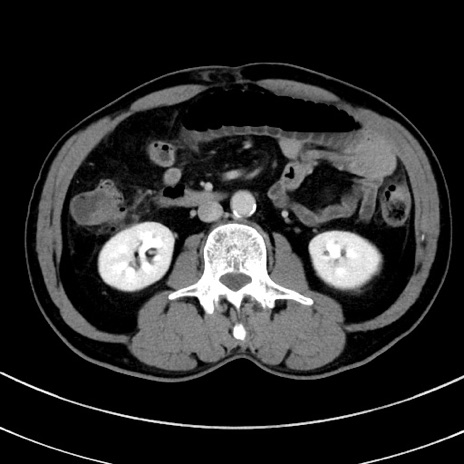

冠状断像

症例8(横断像)

【症例】 60歳代男性

【主訴】 黒色吐物

【現病歴】 4日前から嘔気自覚、2日前の朝食後にも嘔気あり、自分で手で嘔吐反射起こし嘔吐したところ血が混ざっていたため受診。

【既往歴】 5年前汎発性腹膜炎を伴う急性虫垂炎で手術、高血圧、前立腺肥大症、高脂血症

【身体所見】 腹部正中に手術癩痕あり 腹部平坦・軟圧痛なし膨満感あり

【データ】WBC 8400、CRP 4.54